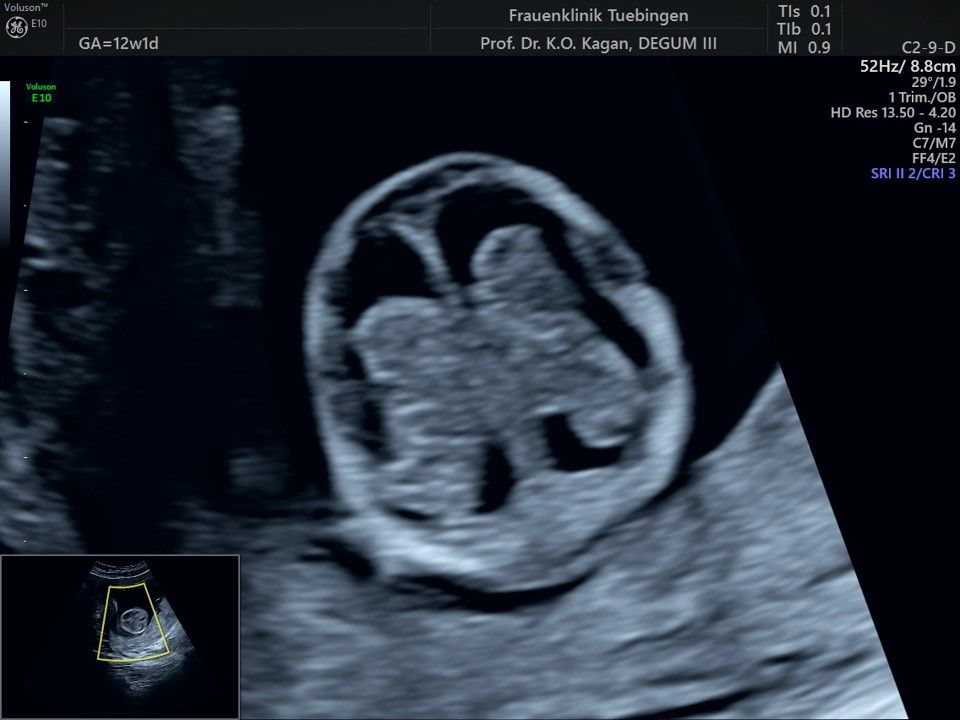

Im Rahmen des Ersttrimester-Screenings untersuchen wir die Organe des Feten mittels Ultraschall. Dabei machen wir auch gerne ein Bild für Sie.

Obwohl der Fet zu diesem Zeitpunkt erst zwischen 5 und 8cm groß ist, lassen sich bereits etwa die Hälfte aller schwerwiegenden Fehlbildungen erkennen bzw. ausschließen. Sollten wir eine Auffälligkeit sehen, werden wir mit Ihnen den Befund und das weitere Vorgehen ausführlich besprechen.

Fetale Anatomie

Herz